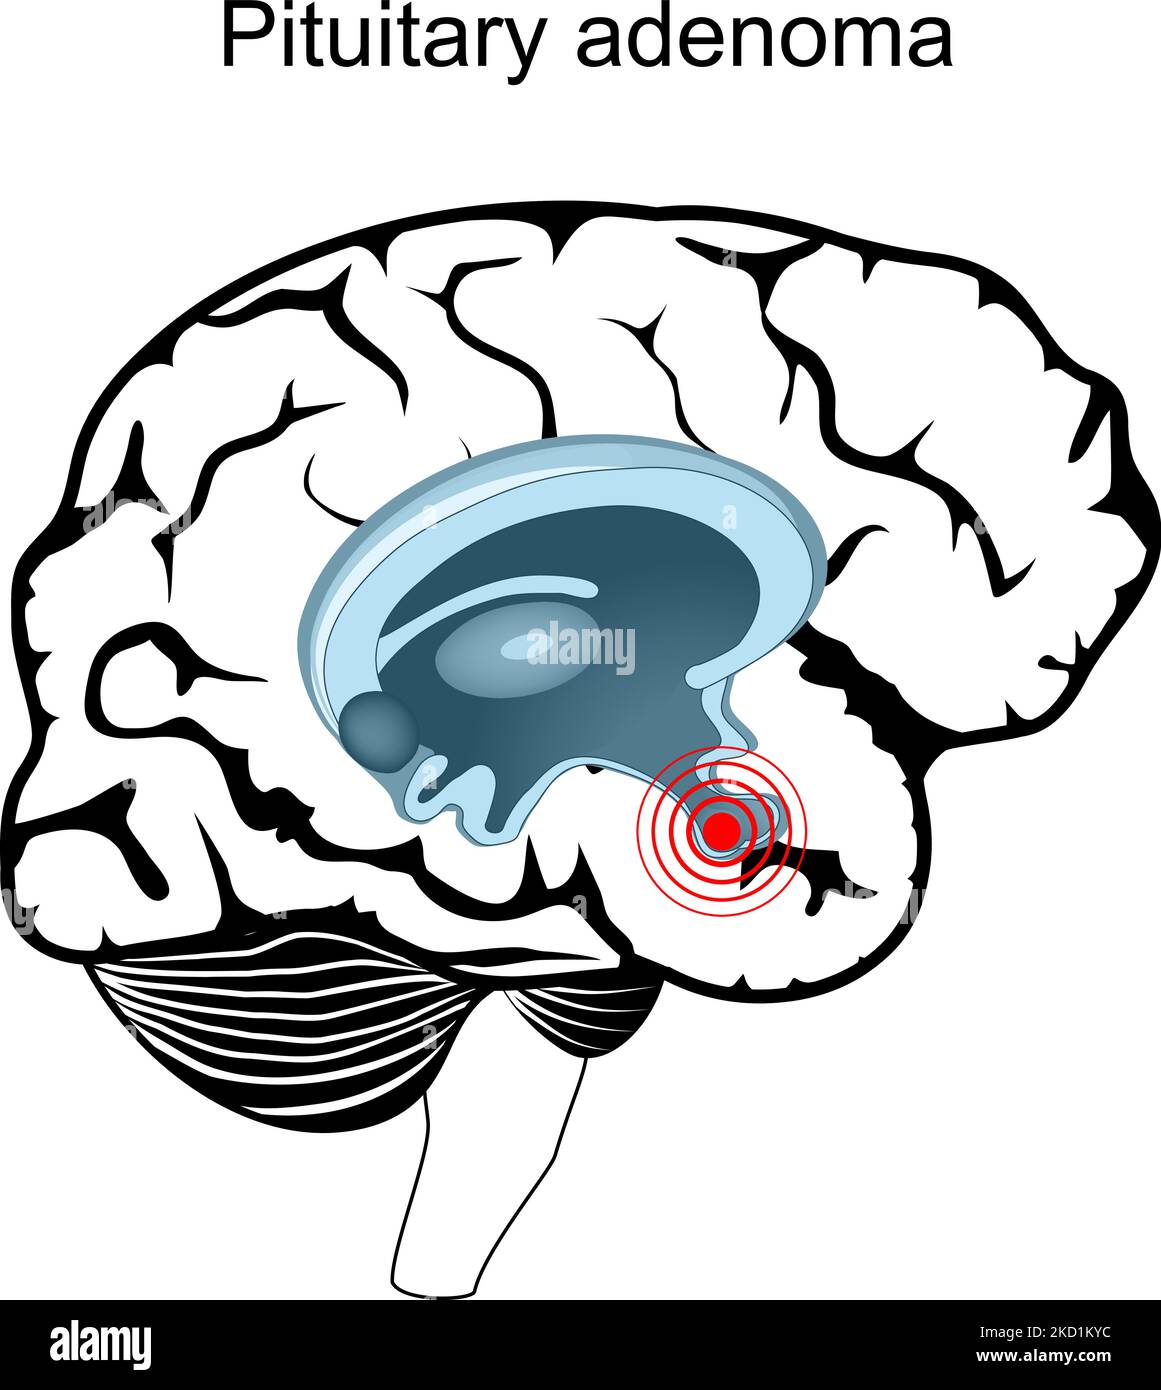

RF2KD1KYC–Adenoma ipofisario. Sezione trasversale del cervello umano. Primo piano di ipofisi. Ghiandola endocrina. Poster vettoriale